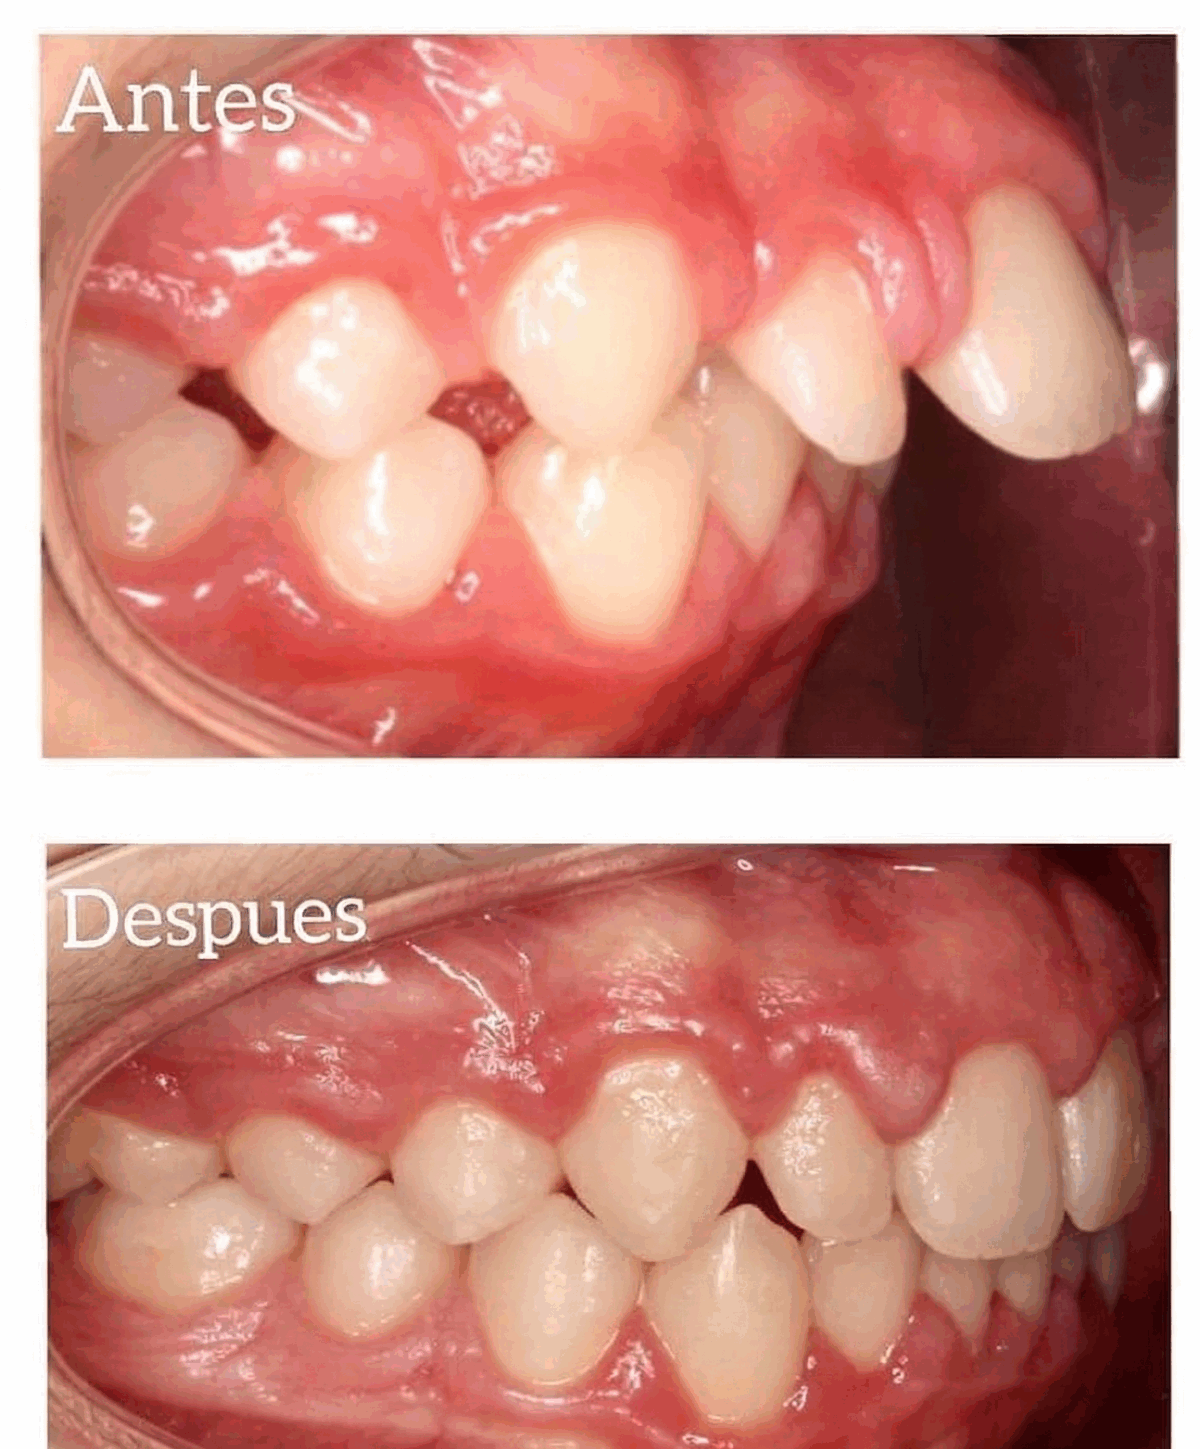

Casos reales de ortodoncia invisalign

Resultados que transforman sonrisas